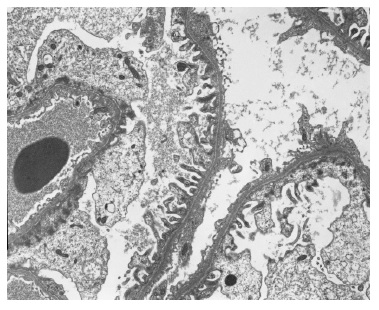

The light microscopy sample was representative only of the medullary region. The immunofluorescence (IF) sample had four glomeruli and was negative (IgG, IgA, C3, kappa and lambda). Electron microscopy (EM) revealed one apparently normal glomerulus except for markedly reduced glomerular basement membrane (GBM) thickness, varying between 83nm e 167nm (reference values: 250-350nm) (Figures 2 and 3). Beyond GBM thinning there were no other changes (such as lamellation, irregular contours or heterogeneity of the GBM). The absence of light microscopy implies the loss of valuable information such as the exclusion of mesangial proliferation or segmental/global glomerulosclerosis (importante for IgA nephropathy). Nonetheless, negative IF suggests that this diagnosis is less probable. Also, EM did not show any mesangial deposits (with the limitation of a small sample since only 1 glomerulus was present). Considering biopsy findings and benign clinical evolution (patient with stable normal kidney function and no proteinuria for more than two years of follow-up) a diagnosis of thin membrane disease was made. It should be stressed that although X-linked Alport syndrome occurs with GBM lamellation, in early stages of the disease only thinning of the basement membrane may be present (although it usually occurs with intermitente GBM lamellation).

Figure 2 Electron microscopy x5000